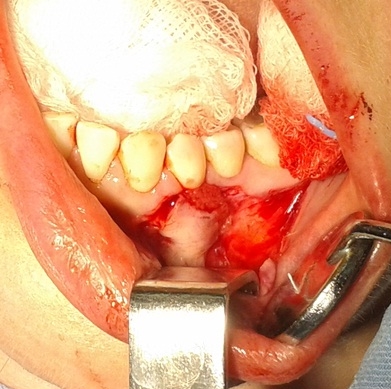

Bogata w płytki i leukocyty fibryna jest stosowana w regeneracji tkanek od ponad 15 lat. Pozytywny wpływ PRF (platelet-rich fibrin) na regenerację tkanek miękkich jest niewątpliwy, bezsporny i częściowo udowodniony w badaniach klinicznych i analizach biochemicznych. Wpływ PRF na regenerację tkanki kostnej jest obserwowany klinicznie, ale nadal niedostatecznie poznany jest mechanizm tego zjawiska.

Platelet- and leukocyte-rich-fibrin has been used in regeneration of tissue for more than 15 years. The positive influence of PRF on the regeneration of soft tissue is undoubtedly, without question and partially proven in clinical studies and biochemical analysis. Influence of PRF on regeneration of bone tissue is observed clinically but the mechanism of this phenomenon is still not sufficiently known.